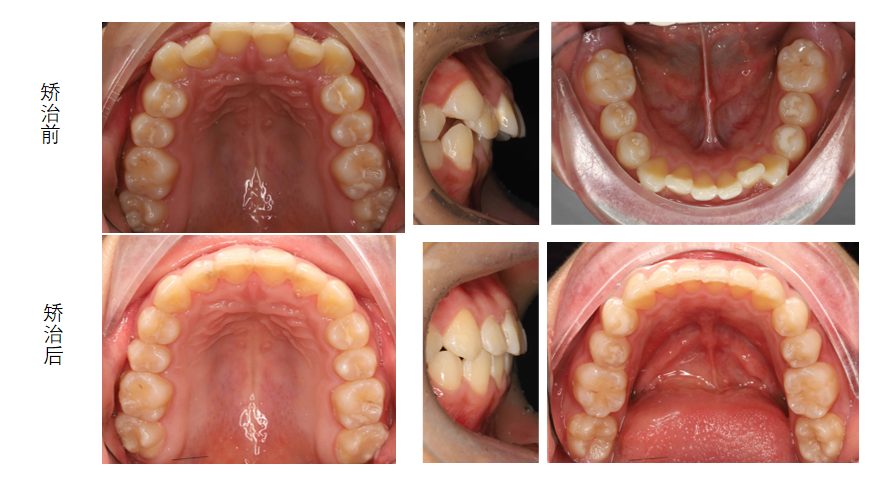

月月矫治前后对比